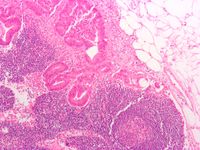

![]() Lymph node, showing (1) capsule, (2) subcapsular sinus, (3) germinal centers, (4) lymphoid nodule, (5) trabeculae. | |

تُمَيَّزُ في العقد تحت المجهر منطقتان: محيطية وتدعى القشر cortex، ومركزية وتدعى اللب medulla. أما القشر فيتألف من مساكن عدة مختلفة في حجمها وشكلها، يفصل بعضها عن بعض الحجب الضامة، ويتوضع في داخلها على شكل أجربة أو عقيدات nodules مجموعات خلوية لمفية تتكثف بشدة في محيطها وتقل في مركزها، ليظهر في شكل نير، ويدعى بالمركز النتوج germinal center، وتُشاهد فيه خلايا أرومة اللمفاوية lymphoblast وخلايا لمفية lymphocyte وخلايا مصورية، وتحوي جميعها الأضداد، وتُشاهد أيضاً البالعات. تكون خلايا العقيدات اللمفية القريبة من محيط القشر من نوع البائية B، وأما التي تكون قريبة من باطن القشر فتكون من نوع التائية T. إن هذا النوع الأخير من الخلايا اللمفية لا يصنع في العقد، بل في نقي العظام، ثم ينتقل إلى التوتة (التيموس)، وفيها يتم نضجه، ثم ينتقل عن طريق الدم إلى العقد اللمفية والطحال.

تفصل العقيدات عن الحجب الضامة مسافات تدعى الجيوب القشرية cortex sinus، تمتد لمنطقة اللب، وتتفرع هناك وتتصل مع محيط العقدة بجيوب ما تحت المحفظة subcapsular sinus. يجري في هذه الجيوب السائل اللمفي الوارد عن طريق الأوعية اللمفية الواردة إلى سطح العقدة، ماراً بالمنطقة القشرية، دافعاً الخلايا اللمفية وما تحمله من أضداد إلى المنطقة اللبية، حيث تتشكل الأوعية اللمفية الصادرة لتخرج مع ما تحمل من السُّرَّة.

إن المنطقة اللبية أقل كثافة من القشر، ويغلب على عناصرها الخلوية شكل حبال تتداخل مع التركيب الشبكي للألياف والخلايا الشبكية، والفروع الدقيقة الانتهائية للحجب الضامة.